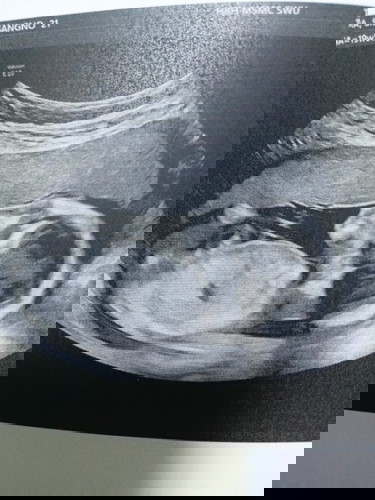

แม่ๆช่วยตั้งชื่อให้หนอ่ยค่ะ แม่ .น. พ่อ .บ. #ลูกชายค่ะ👨👩👦

ตอนนี้19 สัปดาห์ 6 วันแล้วค่ะ #ขอบคุณล่วงหน้านะคะ🙏